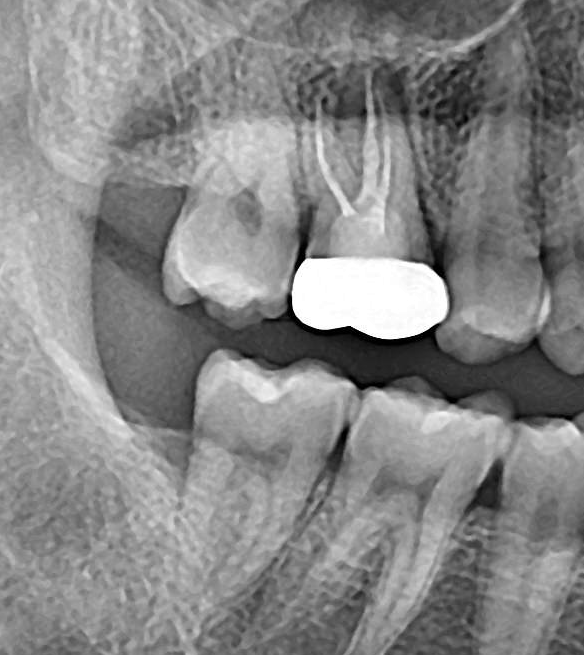

2. 두 치과 모두 뿌리염증이 있다고만 하고 어느 정도인지는 구체적으로 설명을 안 해줬습니다. 사진 상으로 어떤 정도인지 궁금합니다(비교용으로 그간 찍었던 사진을 같이 첨부했습니다) 최근 파노라마를 보면 오른쪽 신경 옆쪽으로 약간 검은 음영이 있는데 이게 뿌리 염증일까요?

그리고 최근 치근단 사진을 보면 신경에서 하얗게 치료된 부분 위로 검은 부분이 보이는데 신경치료가 완전하게 되지 않은 게 맞을까요?

2022년 8월 치근단

23년 6월 파노라마, 치근단

-사진상으로 보면 재신경치료를 하시는것보다는 발치를 해야될 가능성이 높아 보이네요.